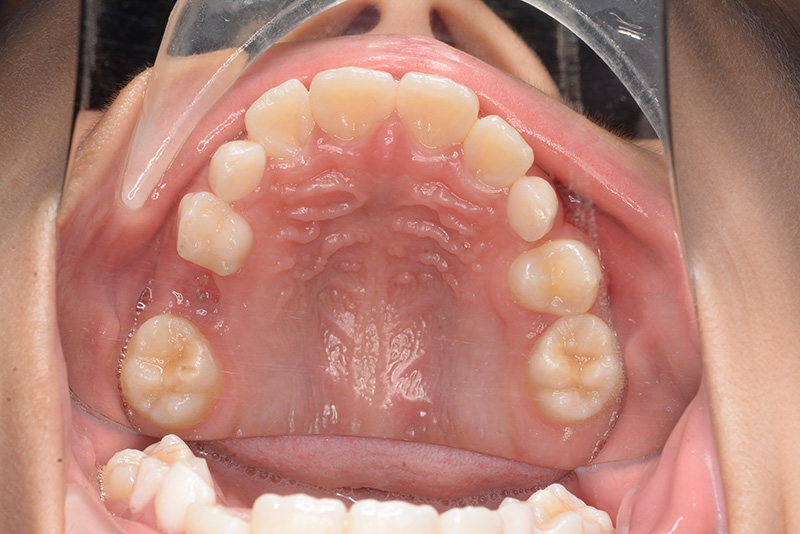

| パノラマ所見 | 上顎両側6、特に左側6は近心傾斜が認められ、両側5の萌出スペース不足が認められた。 |

| 批評・予后 | 早期に6の遠心移動を行いナンスのホールディングアーチにて保隙をした結果、5は良好な状態で萌出できたように思う。 今後は永久歯列完成まで経過観察を行っていく予定である。 |